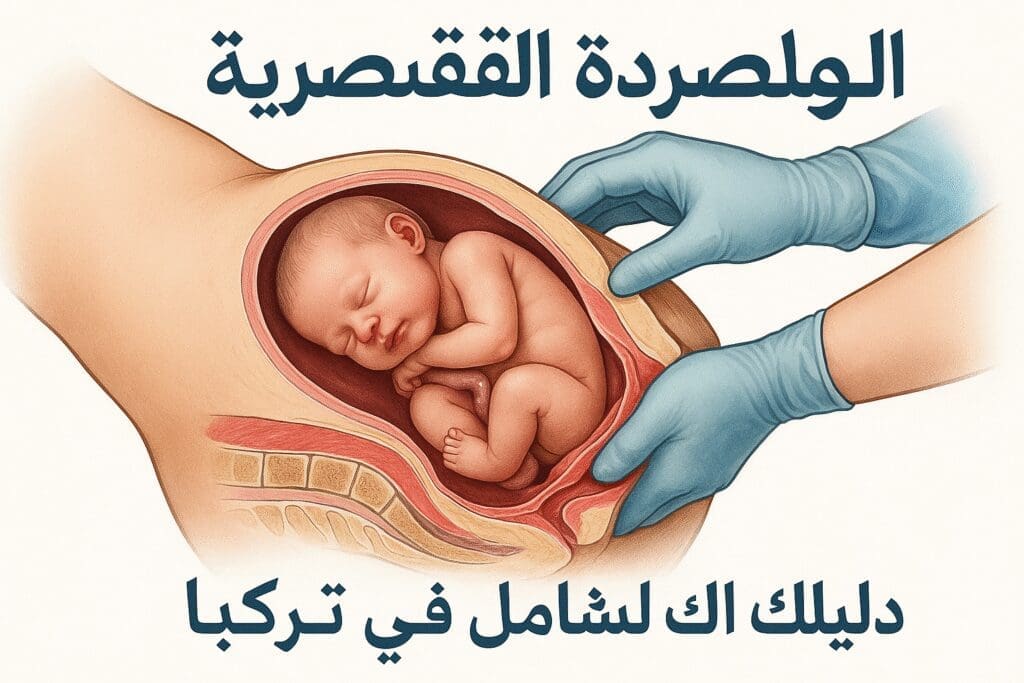

بوابتك للعلاج في تركيا

تضم شبكتنا المتكاملة مستشفيات رفيعة المستوى وأطباء متخصصين ومرافق طبية حديثة، مما يمكننا من تغطية مجموعة واسعة من التخصصات الطبية مع اكثر الأطباء خبرة وبأسعار منطقية.

لما عليك اختيارنا للعلاج في تركيا

لا يمكن لأي مشفى في العالم مهما بلغت امكانياته أن يعالج جميع الحالات بنفس الكفاءة، لذا جمعنا لكم مشافي وأطباء تركيا في شبكة طبية واحدة لنقدم اكفأ العلاجات وبأقل الأسعار